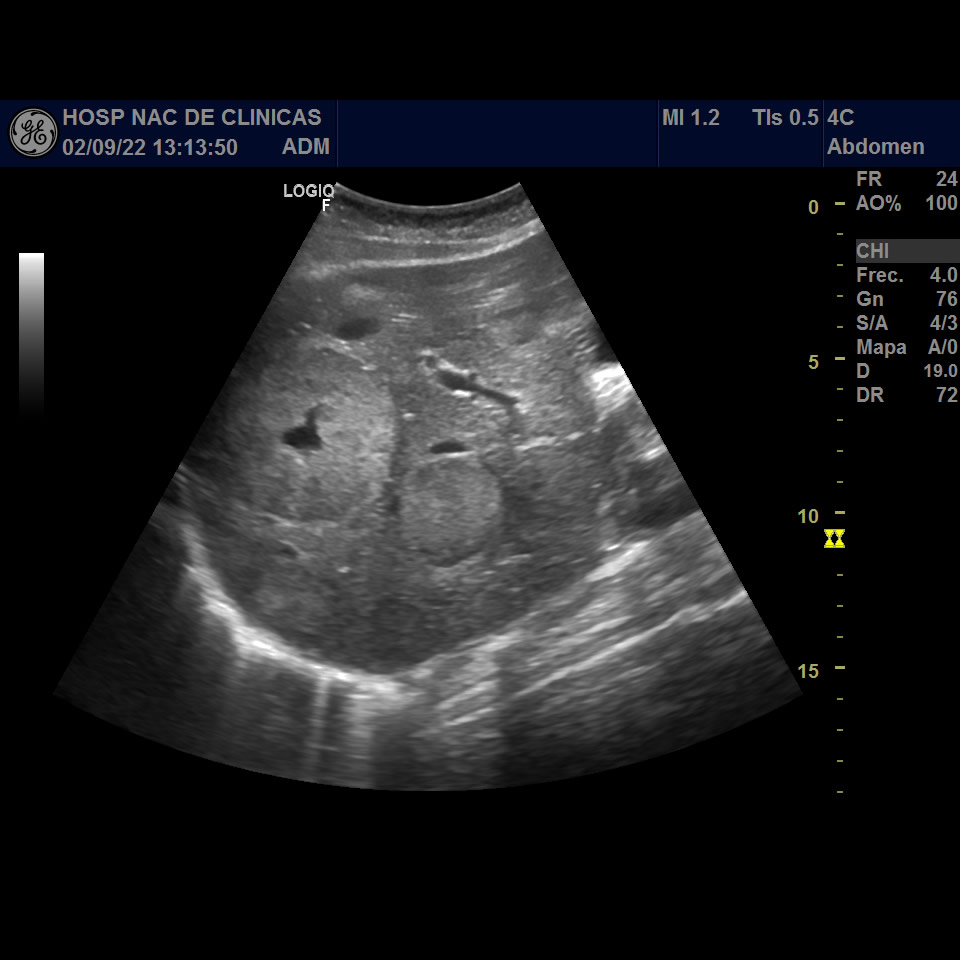

Mujer, 32 años, dolor abdominal